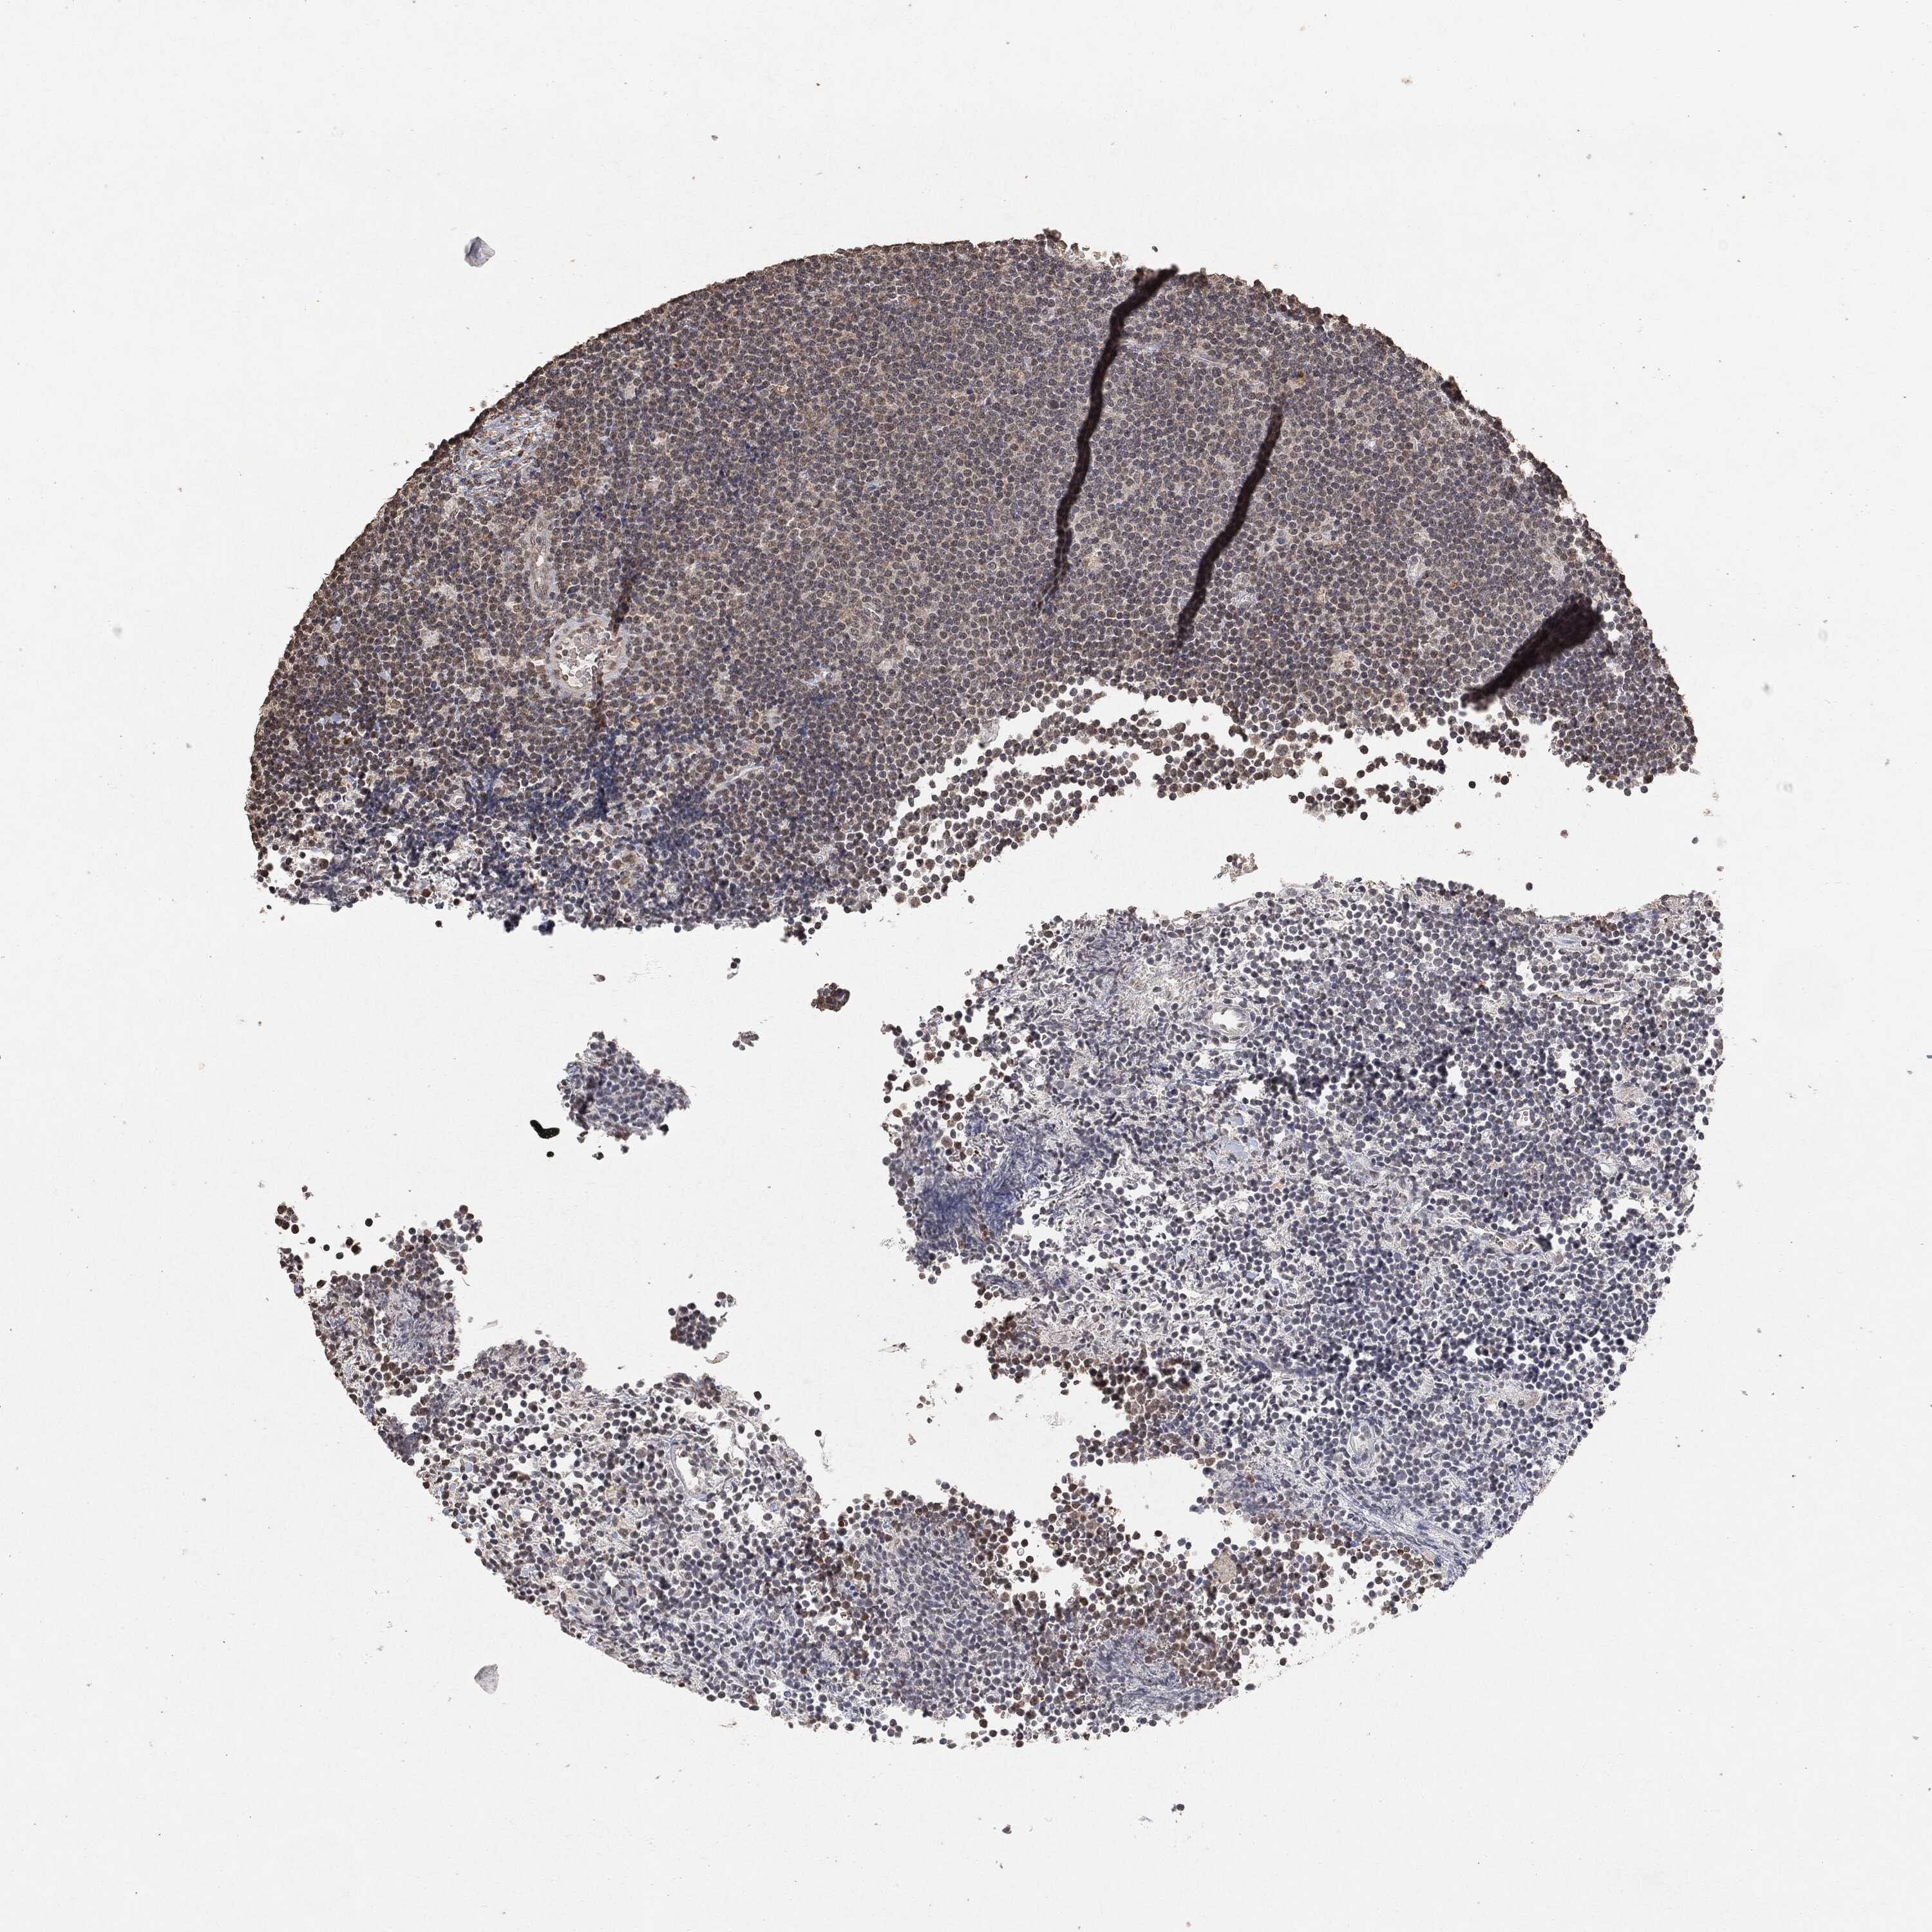

CANCER LYMPHOMA Show tissue menu

LYMPHOMA - Protein expressioni

A mouse-over function shows sample information and annotation data. Click on an image to view it in a full screen mode. Samples can be filtered based on level of antibody staining by selecting one or several of the following categories: high, medium, low and not detected. The assay and annotation is described here.

Each image is clickable and will lead to virtual microscopy that enables deeper exploration of all samples and also displays staining intensity scores, fraction scores and subcellular localization as well as patient and tissue information for each sample.

Malignant lymphoma, non-Hodgkin's type, High grade

Hodgkin's disease, NOS

Malignant lymphoma, non-Hodgkin's type, Low grade